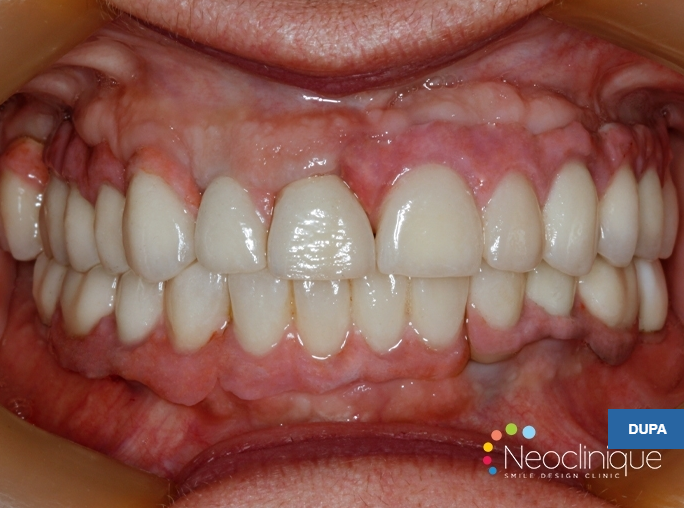

Pacienta în vârstă de 46 ani se prezintă în clinică având edentație uniterminală bimaxilară (maxilar 1 modificare, mandibulă 4 modificari) cu parodontopatie marginală cronică profundă, dinții prezentând mobilitate grad 3, o proteză mobilă parțial acrilică incorect adaptată campului edentat cauzând inflamația mucoaselor pe care se sprijinea, restaurări protetice fixe metalo-ceramice incorect adaptate, unele fixate provizoriu pe bonturi fracturate, reacții periapicale.